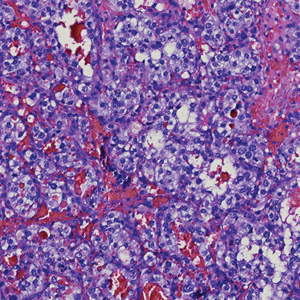

Cystic Presentation of High-Grade Ductal Carcinoma In Situ in an Inframammary Accessory NippleAugust 23, 2023DermatopathologyNonmelanoma Skin Cancer